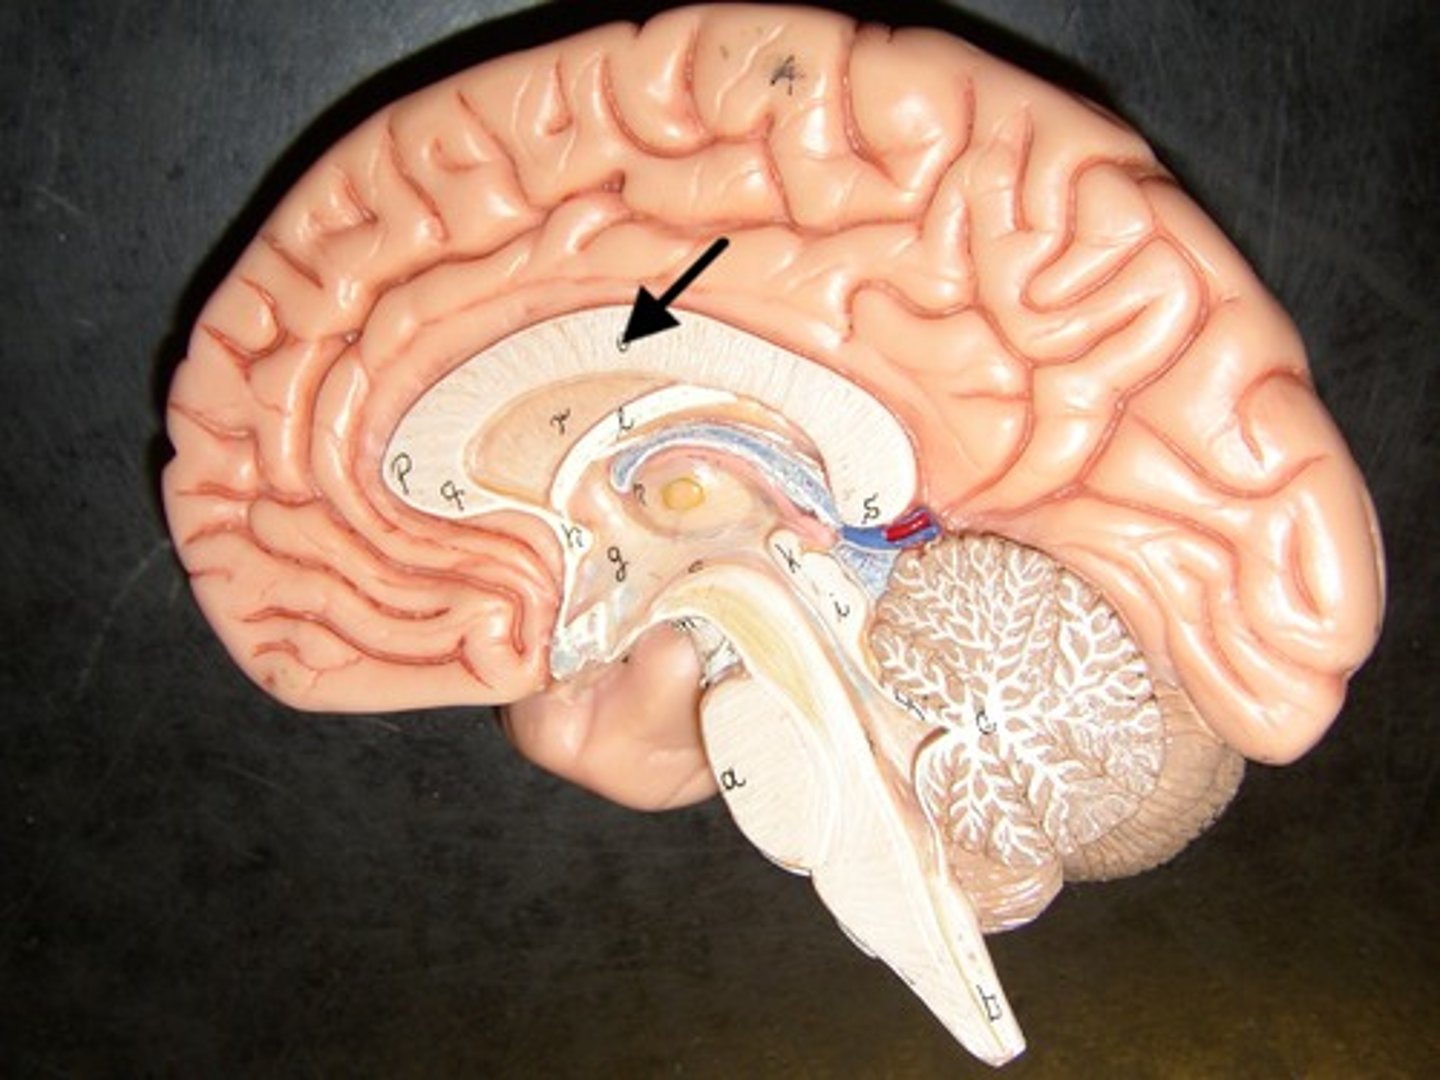

Cerebral Medulla

White matter,

Myelinated nerve tracts inside the gray matter that are responsible for communication between cerebral areas and between cerebral cortex and lower CNS centers,

Corpus callosum

Corpus Callosum

Dense band of myelinated nerve tracts that allow communication between left and right cerebral hemispheres

Epithalamus

Forms the roof of the 3rd ventricle,

Houses the pineal gland or body (an endocrine gland) (Melatonin production: sleep/wake cycle),

Includes the choroid plexus (forms cerebrospinal fluid- CSF)

Choroid Plexus

Forms Cerebrospinal Fluid

Choroid Plexus

Pineal Gland

Melatonin Production (sleep/wake cycle)

3rd Ventricle